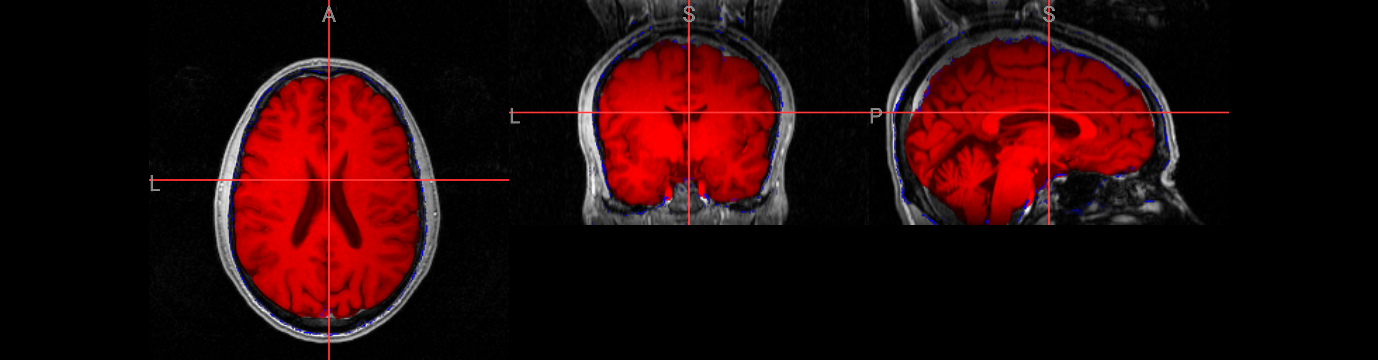

Brain extraction is a fundamental preprocessing step in neuroimaging analysis, particularly critical for structural image segmentation where precision matters most. While BET is straightforward to use, achieving optimal results often requires understanding how to fine-tune parameters for challenging datasets. This interactive version covers the core BET fundamentals, including parameter adjustment techniques for difficult images, and troubleshooting approaches for problematic cases. The hands-on format allows you to experiment with different settings and immediately see their effects on brain extraction quality.